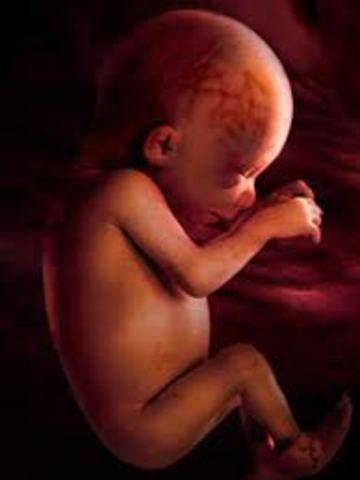

• Month 7

Month 7

• The baby is about 10 to 12 inches long and 1 1/2 to 2 pounds

• The periods of activity followed by periods of rest and quiet.